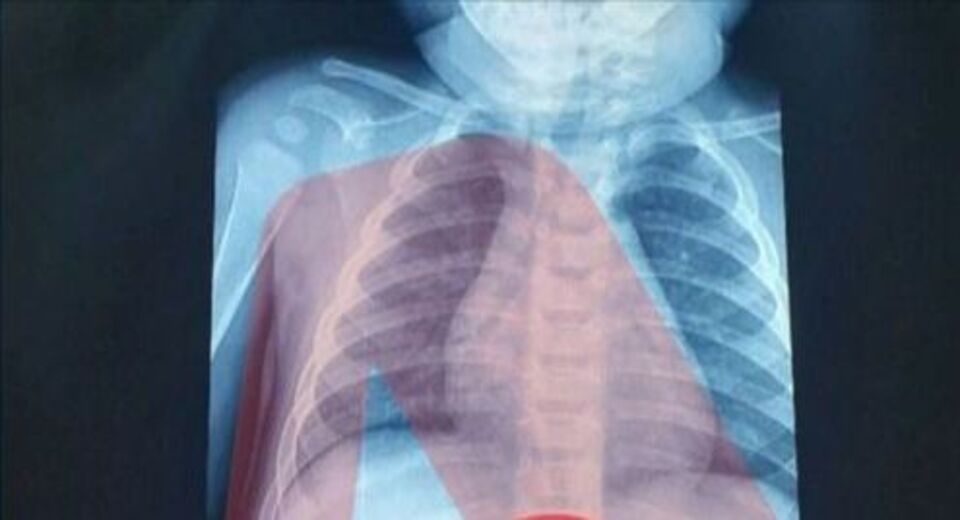

Ένας 3χρονος μεταφέρθηκε εσπευσμένα στο νοσοκομείο, το οποίο κατάπιε ένα ξυραφάκι. Το παιδί αφού έφτασε σε Παίδων της Αθήνας, υποβλήθηκε άμεσα σε ακτινογραφία, η οποία έδειξε ότι όντως υπήρχε το αιχμηρό αντικείμενο στο στομάχι του

Όπως ενημέρωσαν οι γιατροί, τους γονείς του παιδιού, μετά την ακτινογραφία προσδιορίστηκε και το ακριβές σημείο όπου βρέθηκε το ξυραφάκι, ώστε οι χειρουργοί να προχωρήσουν σε επέμβαση αφαίρεσής του με ασφάλεια.